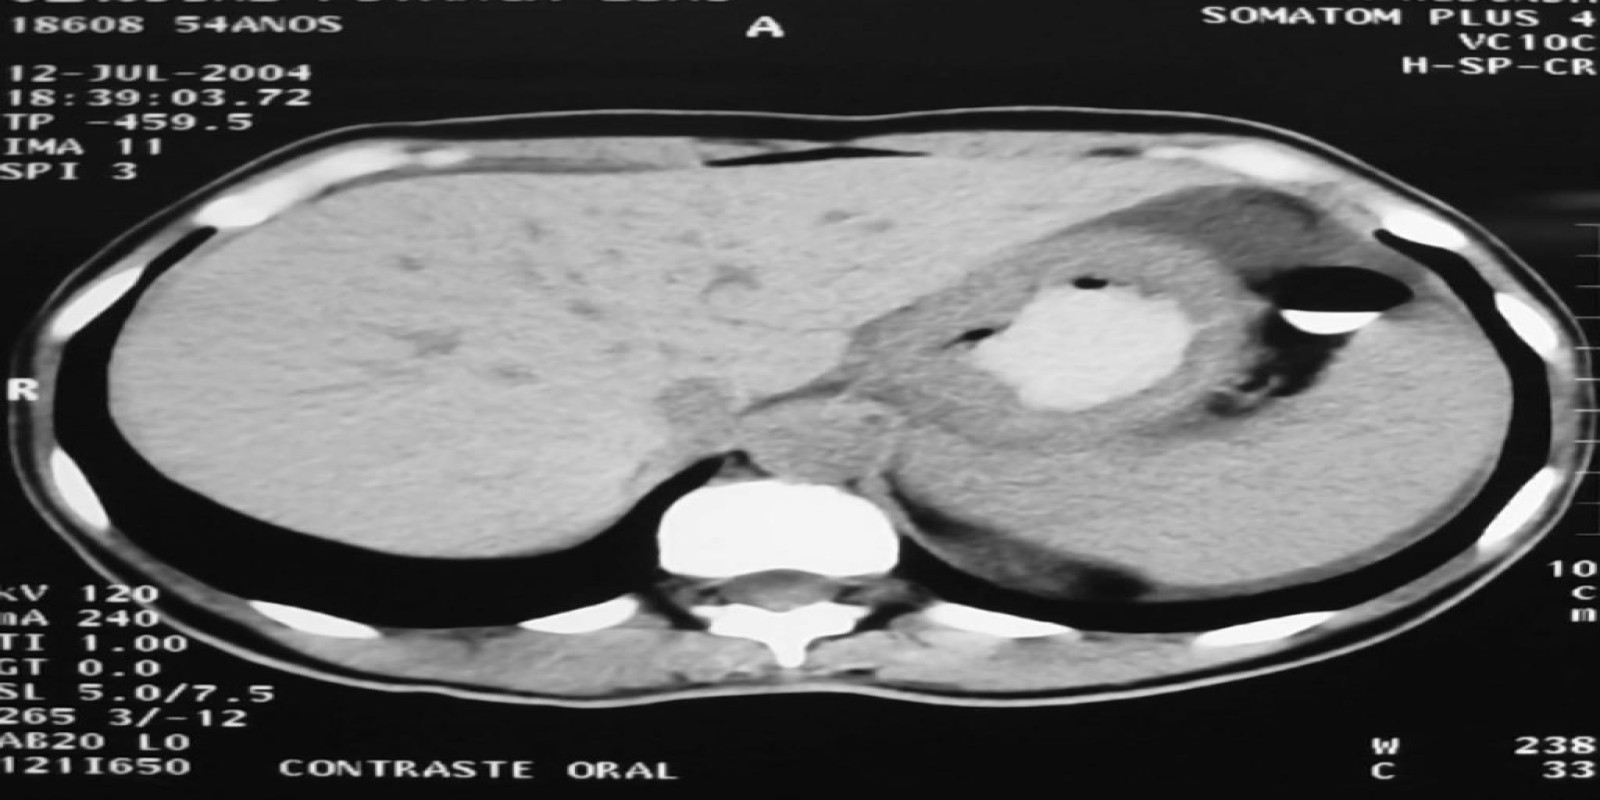

Caso Código 149A de Câncer Gástrico

Cod.: 149A